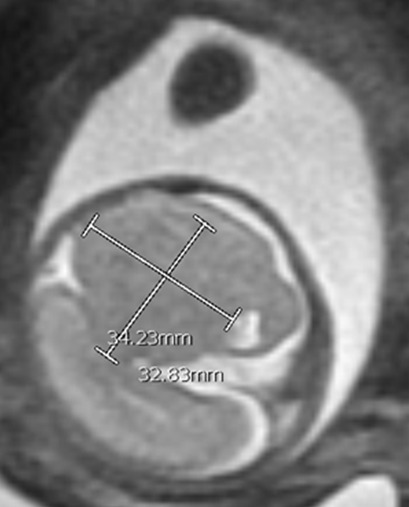

At 23w0d a limited fetal MRI was repeated (Figure 4). This study demonstrated, again, the supratentorial left hemispheric mass measuring 3.3 x 3.5 x 2.4 cm within the cerebrum of Twin A. Most notably, there was an interval increase in the size of the mass relative to the skull diameter, as well as a prominent mass effect on the contralateral hemisphere with an associated midline shift. This second fetal MRI finding was interpreted as most consistent with an enlarging intracranial neoplasm with the differential diagnoses including astrocytoma, intracranial teratoma, and glioblastoma multiforme; however, no distinctive features were noted to confirm one of these diagnoses. The interval growth of the mass was interpreted as characteristic of an aggressive fetal neoplasm; therefore, a migrational anomaly was seen as less likely.